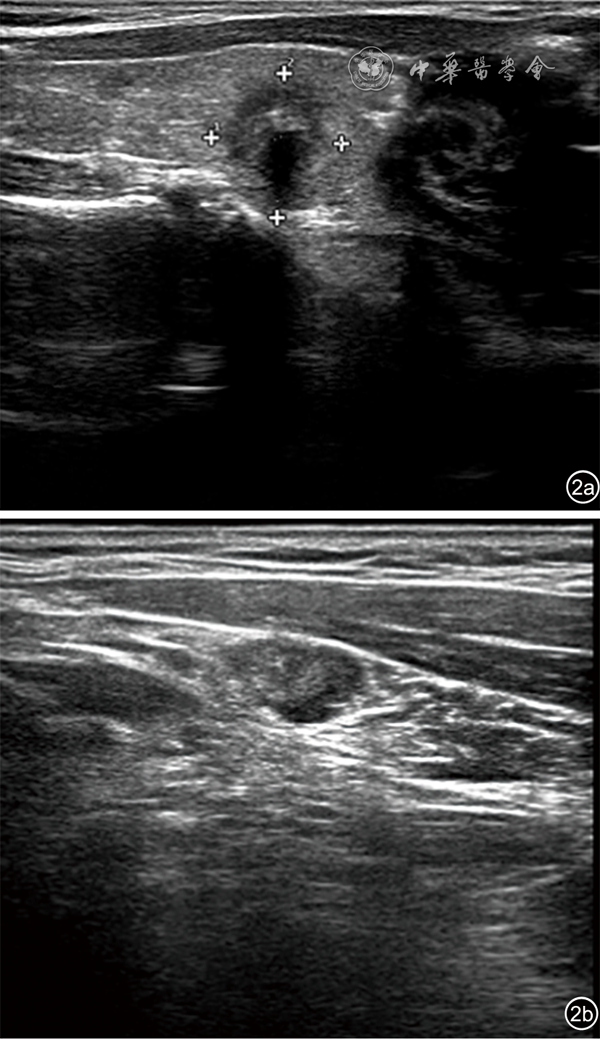

图2 33岁女性患者甲状腺右叶10.1 mm×11.2 mm低回声结节,超声表现为结节横径<20 mm(图a),结节纵径≥10 mm(图b)。病理诊断为甲状腺乳头状癌(右侧),颈侧区淋巴结见转移(右侧)